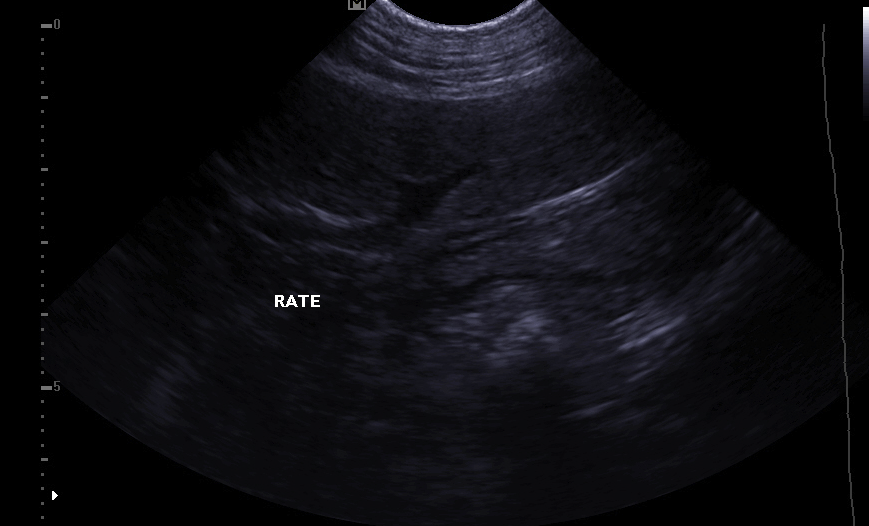

Echocardiography:

It makes it possible to visualize the different parts of the heart (walls, cavities, valves) and to identify any anomalies that prevent correct cardiac functioning. In case of heart failure, echocardiography also allows regular monitoring of cardiac morphology. It is then easier to readjust the treatment in place.